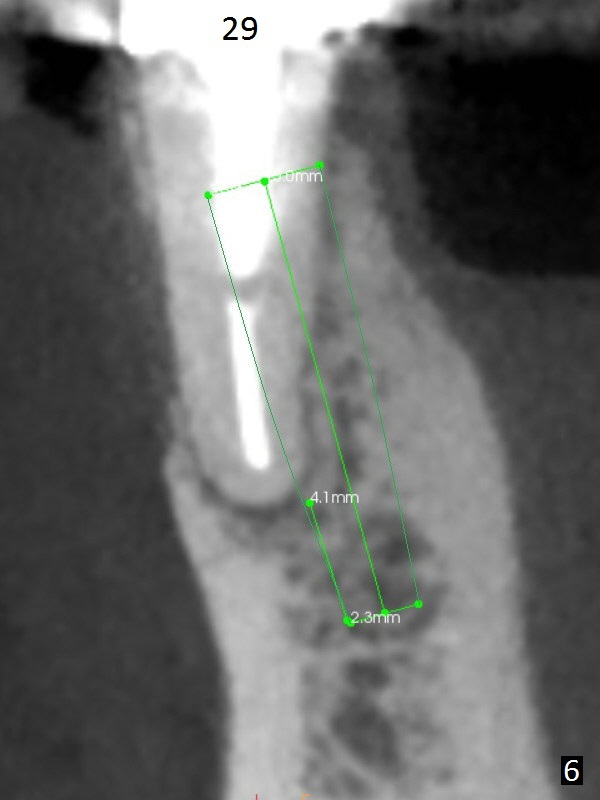

A 50-year-old man has pain and swelling buccal to the tooth #29 with large distal radiolucency (Fig.1 *). The bridge will be sectioned between #30 and 31. The mesial segment of the bridge is expected to separate from #29 post space; the mesial abutment is presumed to have vertical fracture (Fig.4 red line or root perforation due to oversized post (>)). After intraligamental injection, extraction and no Antibiotic treatment, a narrow long implant (Fig.6,7: 3.8x15 or 13 mm) will be placed as mesial and lingual as possible to avoid the buccal bony defect (Fig.5 >; repaired with Osteotape or PRF membrane) and the Mental Loop (Fig.1 >).

The ridge at #30 is pointed (Fig.2) and going to be resected (Fig.3 black area) to receive a narrow, short implant (3.8x8.5 mm). A splinted immediate provisional will be fabricated following placement of a 4.5x4(5) mm abutment at #30 (Fig.2,3). Take Alginate impression when the patient arrives in case the tooth #31 is also non-salvageable.